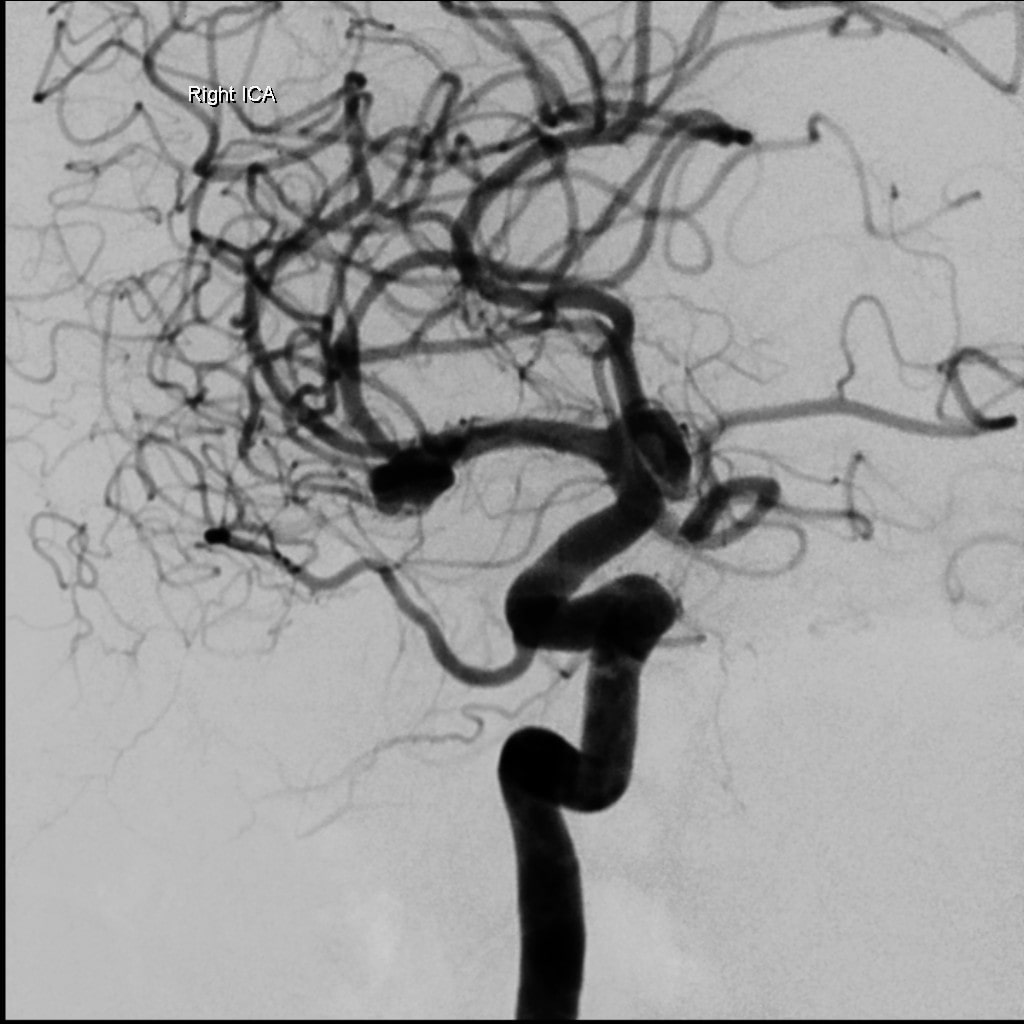

Le coiling se fait à travers des micro-cathéters introduits dans les artères, en général à partir du pli de l’aine. A travers ces micro-cathéters sont introduites des microspires métalliques qui vont combler l’anévrysme et éviter un resaignement.